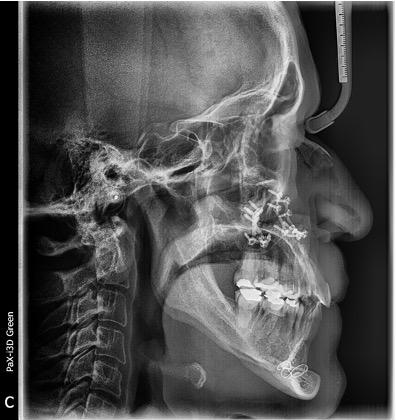

Estudios radiográficos de inicio

En la radiografía lateral de cráneo tenemos (Figura 7) la clase III esquelética con un ANB de -1, hiperdivergencia, aumento de la altura facial inferior, proclinación de los incisivos superiores con 1 a plano palatino de 133°, línea roja sobre la longitud del incisivo superior.

En la radiografía panorámica (Figura 8) se observan 32 dientes presentes

en boca, con la rehabilitación de los órganos dentarios por oclusal, con obturaciones de amalgamas, e incrustaciones, y divergencias radiculares inadecuadas.

Figura 7. Radiografía lateral de cráneo. Figura 8. Radiografía panorámica.